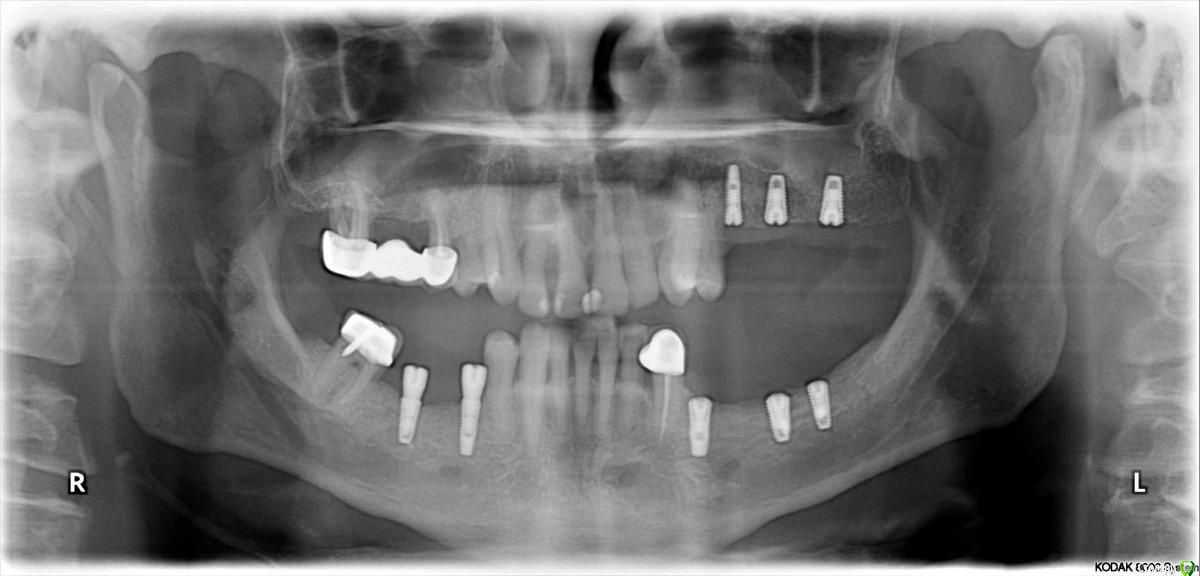

Сегодня опять ругался с ортопедом. Снова сделал уступ 1мм. Не надо так! Стоит формирователь,прекрасная коническая шахта с достаточным объемом закрывающей десны в основании,зачем ее зажимать плоской шляпой? Работа должна садится легко. У платформы десну зажимать нельзя!

Фото по теме не мои, насобирал в фб.

У Вас получилось «не благодаря ,а вопреки». На каком то этапе наросла кость на плечо импланта и все живет . Обычно получается как r_b показал(кошмар! Такую работу запороли). В общем,на авось прокатит надеяться не надо,лучше не давать повода и контролировать каждый этап. И беречь десну,будет прикреплённая десна-будет и кость-будет жив имплант.